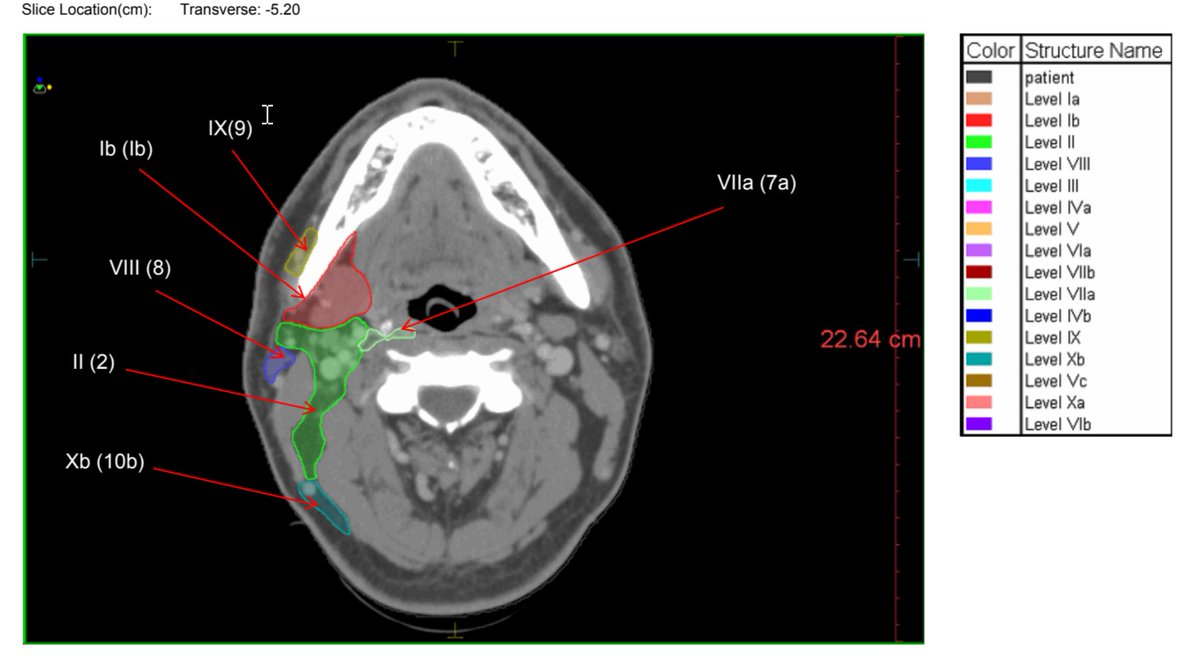

This has helped other #radonc trainees, so sharing my annotated consensus neck nodal guidelines slide deck here (Grégoire et al.)

I put labels throughout as the colors were hard to follow, making it easier to help with h&n contours

Good luck!

drive.google.com/file/d/1WE8SeB…